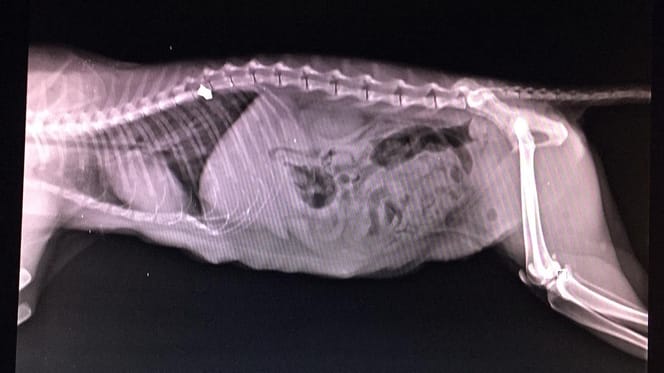

Radiographie du ventre d'un chat

© Huellas de Sarria / Facebook

La radiographie révèle alors qu'une balle est logée dans sa colonne vertébrale. Il est immédiatement clair que le chaton doit être opéré pour déterminer si ce corps étranger est la cause de l'incapacité de Fiuncha à bouger.